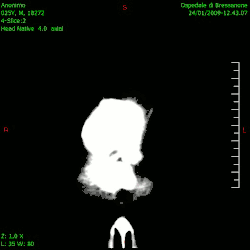

En las imágenes de TC y RM se muestra como una lesión heterogénea, de contorno irregular, que capta contraste en anillo y con un área central necrótica.

Diagnóstico por imagen y glioblastoma

La TC muestra una lesión de morfología irregular, predominantemente hipodensa y fuertemente dishomogénea, debido a la presencia de grandes áreas necróticas de más clara hipodensidad y de áreas sólidas hiperdensas. Estas últimas son la expresión de un rápido crecimiento y por lo tanto de una elevada malignidad. Son frecuentes las zonas hemorrágicas, que van desde pequeños focos a grandes áreas hemáticas que pueden cubrir toda la lesión. Es característica la morfología en "mariposa" si el tumor se asienta en ambos hemisferios a través del cuerpo calloso.

Tras la aplicación de contraste aparecen gruesos anillos alrededor de las áreas necróticas. En la RM, la parte sólida aparece hipointensa en T1 e hiperintensa en T2 con zonas de señal más elevada en las partes de mayor celularidad. Las áreas necróticas, hiperintensas en T2, pueden presentarse hipo-, iso- o hiperintensas en T1 en función del contenido proteico o de productos de la degradación de la hemoglobina. El realce tras el contraste suele ser intenso e irregular en la periferia del tumor e identifica sobre todo la componente celular "proliferativa" de la neoplasia. Son comunes las áreas puntiformes y serpiginosas de ausencia de señal de flujo, asociadas a la presencia de una neovascularización rica. Estos vasos de neoformación patológica carecen de barrera hematoencefálica, lo que explica tanto la abundante impregnación como el edema vasogénico perilesional (véase la sección anterior), debido al paso de líquido al medio extracelular.[72][73]